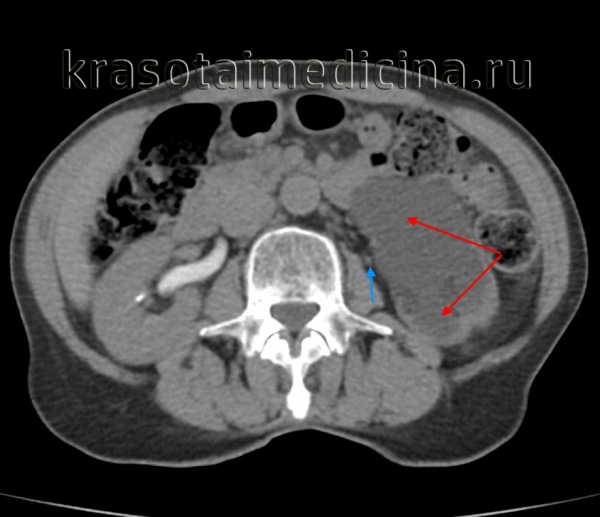

(Слева) КТ с контрастированием в экскреторную фазу после субтотальной колэктомии, аксиальный срез: экстравазация контрастируемой мочи в скопление жидкости вблизи места анастомоза ободочной кишки, вследствие пересечения мочеточника.

(Справа) Ретроградная пиелография: у этого же пациента определяется пересечение левого мочеточника и слабовыраженная экстравазация. На повторной операции было подтверждено пересечение мочеточника.

КТ-урография. Резкое расширение чашечек и лоханки левой почки (красная стрелка), отсутствие контрастирования суженного левого мочеточника (синяя стрелка).